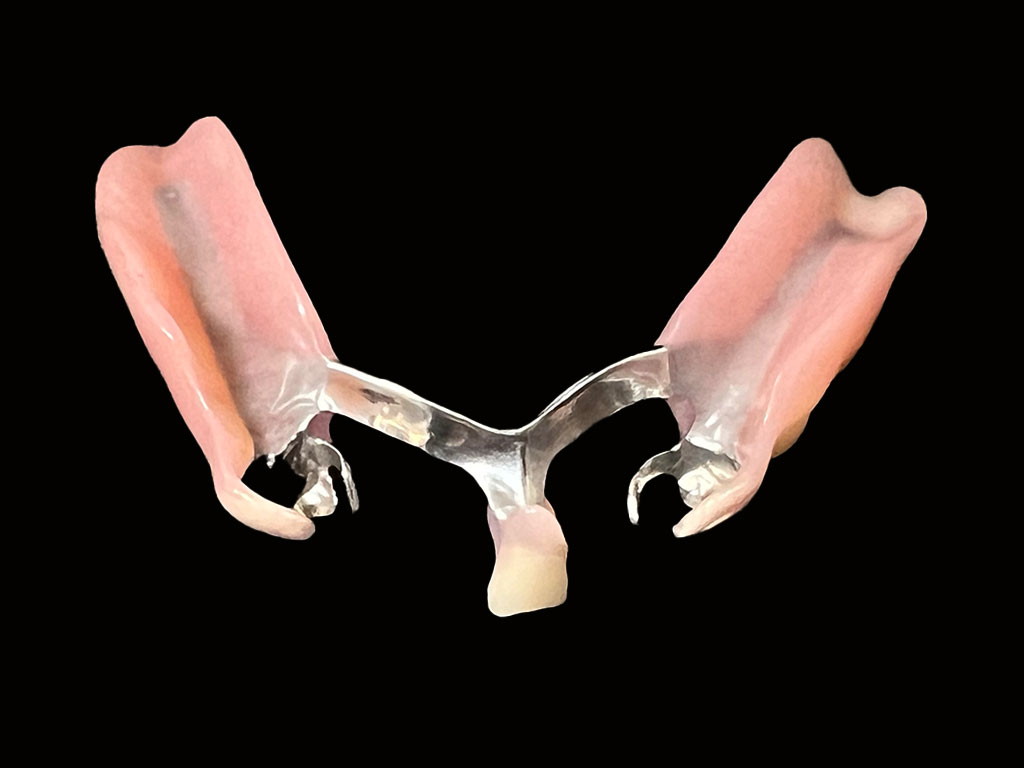

セットした自費の入れ歯1

セットした自費の入れ歯2

下顎左7652番および右14567番が欠損を補う自費の入れ歯

(下顎左431、右3番にメタルクラスプ)

金属部分が目立たない、フィット感がある、入れ歯を支える歯への負担を軽減させるため、下顎左7652番および右14567番が欠損を補う自費の入れ歯を作成。異物感をできるだけ少なくするために、オールプラスチックのスマイルデンチャーは選択せず、舌で触れる部分はメタルで薄く加工することにした。またクラスプも金属のため、緩くなったら締めなおせるというメリットもある。デジタルスキャナーで型取りをして、3Dプリンターで模型を作成し、その精密な顎模型を製作。そして当院専属の入れ歯技工士早澤が入れ歯を精魂込めて製作いたしました。